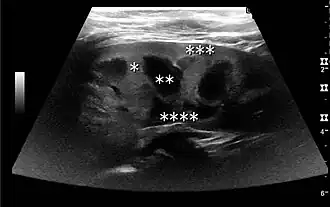

The kidney is divided into parenchyma and renal sinus. The renal sinus is hyperechoic and is composed of calyces, the renal pelvis, fat and the major intrarenal vessels. In the normal kidney, the urinary collecting system in the renal sinus is not visible, but it creates a heteroechoic appearance with the interposed fat and vessels. The parenchyma is more hypoechoic and homogenous and is divided into the outermost cortex and the innermost and slightly less echogenic medullary pyramids. Between the pyramids are the cortical infoldings, called columns of Bertin (Figure 1). In the pediatric patient, it is easier to differentiate the hypoechoic medullar pyramids from the more echogenic peripheral zone of the cortex in the parenchyma rim, as well as the columns of Bertin (Figure 2).[1]

Figure 2. Normal pediatric kidney. * Column of Bertin; ** pyramid; *** cortex; **** sinus.[1] -